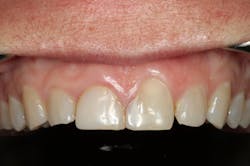

We digitally analyze our esthetics and smile design using the Dawson Diagnostic Wizard (the Dawson Academy). One of our biggest esthetic concerns in this case was caused by a functional issue. As you can see in the photos (figures 1 and 2), the patient has significantly more attritional wear on the right side versus the left. Due to the wear, the right anterior teeth have suffered from more compensatory eruption than the left, which results in uneven gingival architecture and esthetically displeasing length-to-width ratios of the anterior teeth (figures 3 and 4).

When we start to look at our occlusal shots (figures 5 and 6), it is obvious that we have some acidic erosion into dentin as well as significant wear facets from attrition. The pulp chambers of teeth Nos. 8 and 9 are now visible due to the loss of lingual tooth structure.